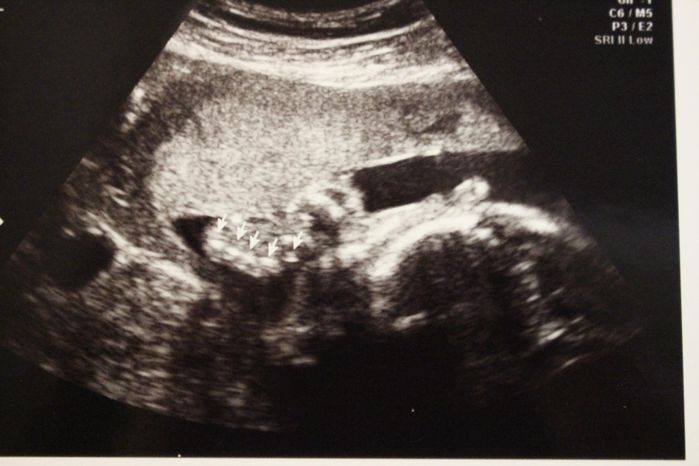

妊娠28週目のエコー写真

指を開いて見せているところ?この頃から「ぽん太」はおなかの中でよく伸びをしていて、胃が押し上げられました。入院してからは毎日誰かの赤ちゃんが誕生し、新生児室のガラス越しに並んだベビーたちを眺める楽しみも加わりました。